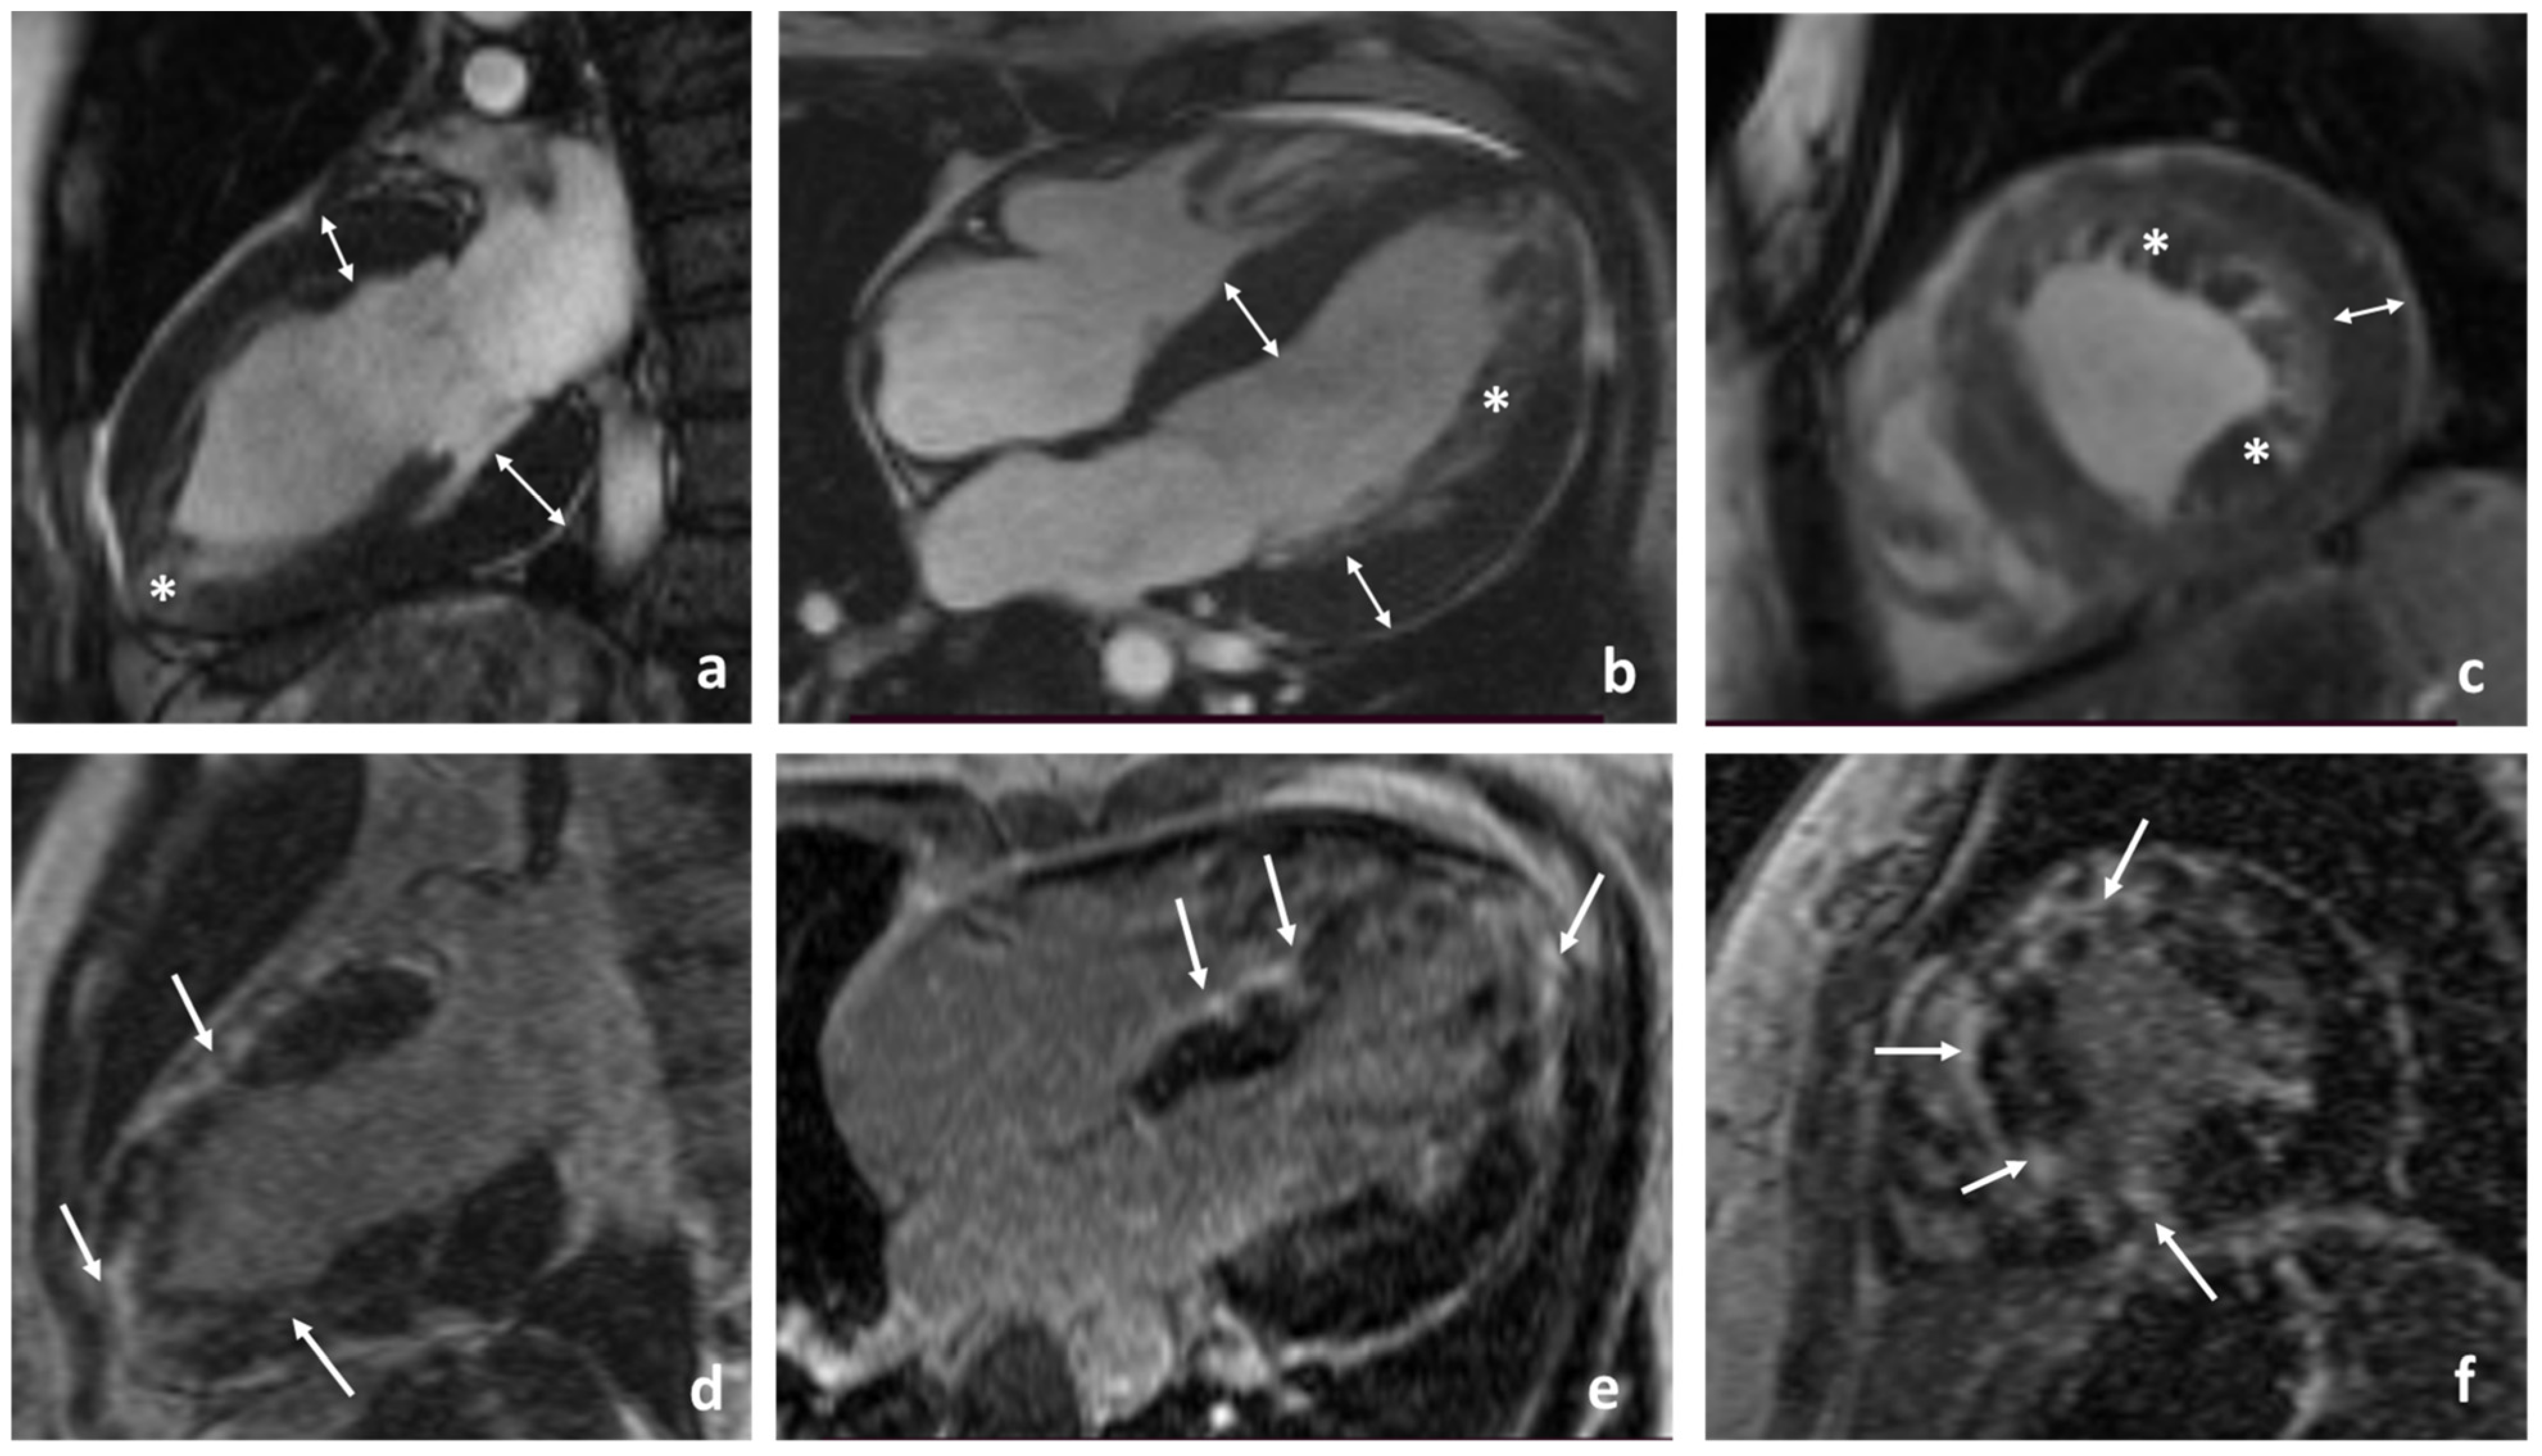

2.1. Clinical Characteristics of the Proband

2.2. Phenotypic Cascade Screening of the Relatives